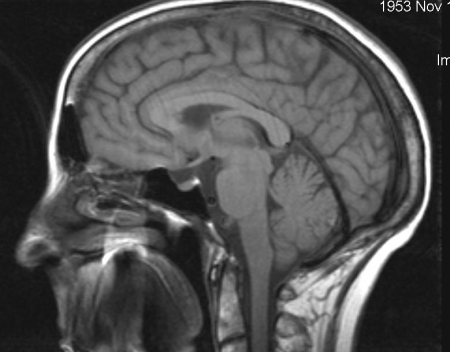

Гипертрофический узловатый глиоз

Генетическое заболевание, при котором образуются доброкачественные опухоли во многих внутренних органах. Причиной заболевания является мутация генов TSC1 и TSC2 . В основе заболевания лежит нарушение тормозного влияния этих генов на избыточное деление клеток.